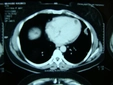

Bu belirtiler, lezyonun yerleşim yeri ve büyüklüğüne göre değişiklik gösterebilir. 4. Tanı YöntemleriYoğun içerikli kistik lezyonların tanısı, çeşitli görüntüleme yöntemleri ve biyopsi ile yapılabilir. Kullanılan başlıca tanı yöntemleri şunlardır:

Bu yöntemler, lezyonun özelliklerini, boyutunu ve içeriğini belirlemeye yardımcı olur. 5. Yoğun İçerikli Kistik Lezyonların TedavisiTedavi planı, lezyonun tipi, boyutu ve hastanın genel sağlık durumu gibi faktörlere bağlı olarak değişir. Yoğun içerikli kistik lezyonların tedavi seçenekleri arasında: